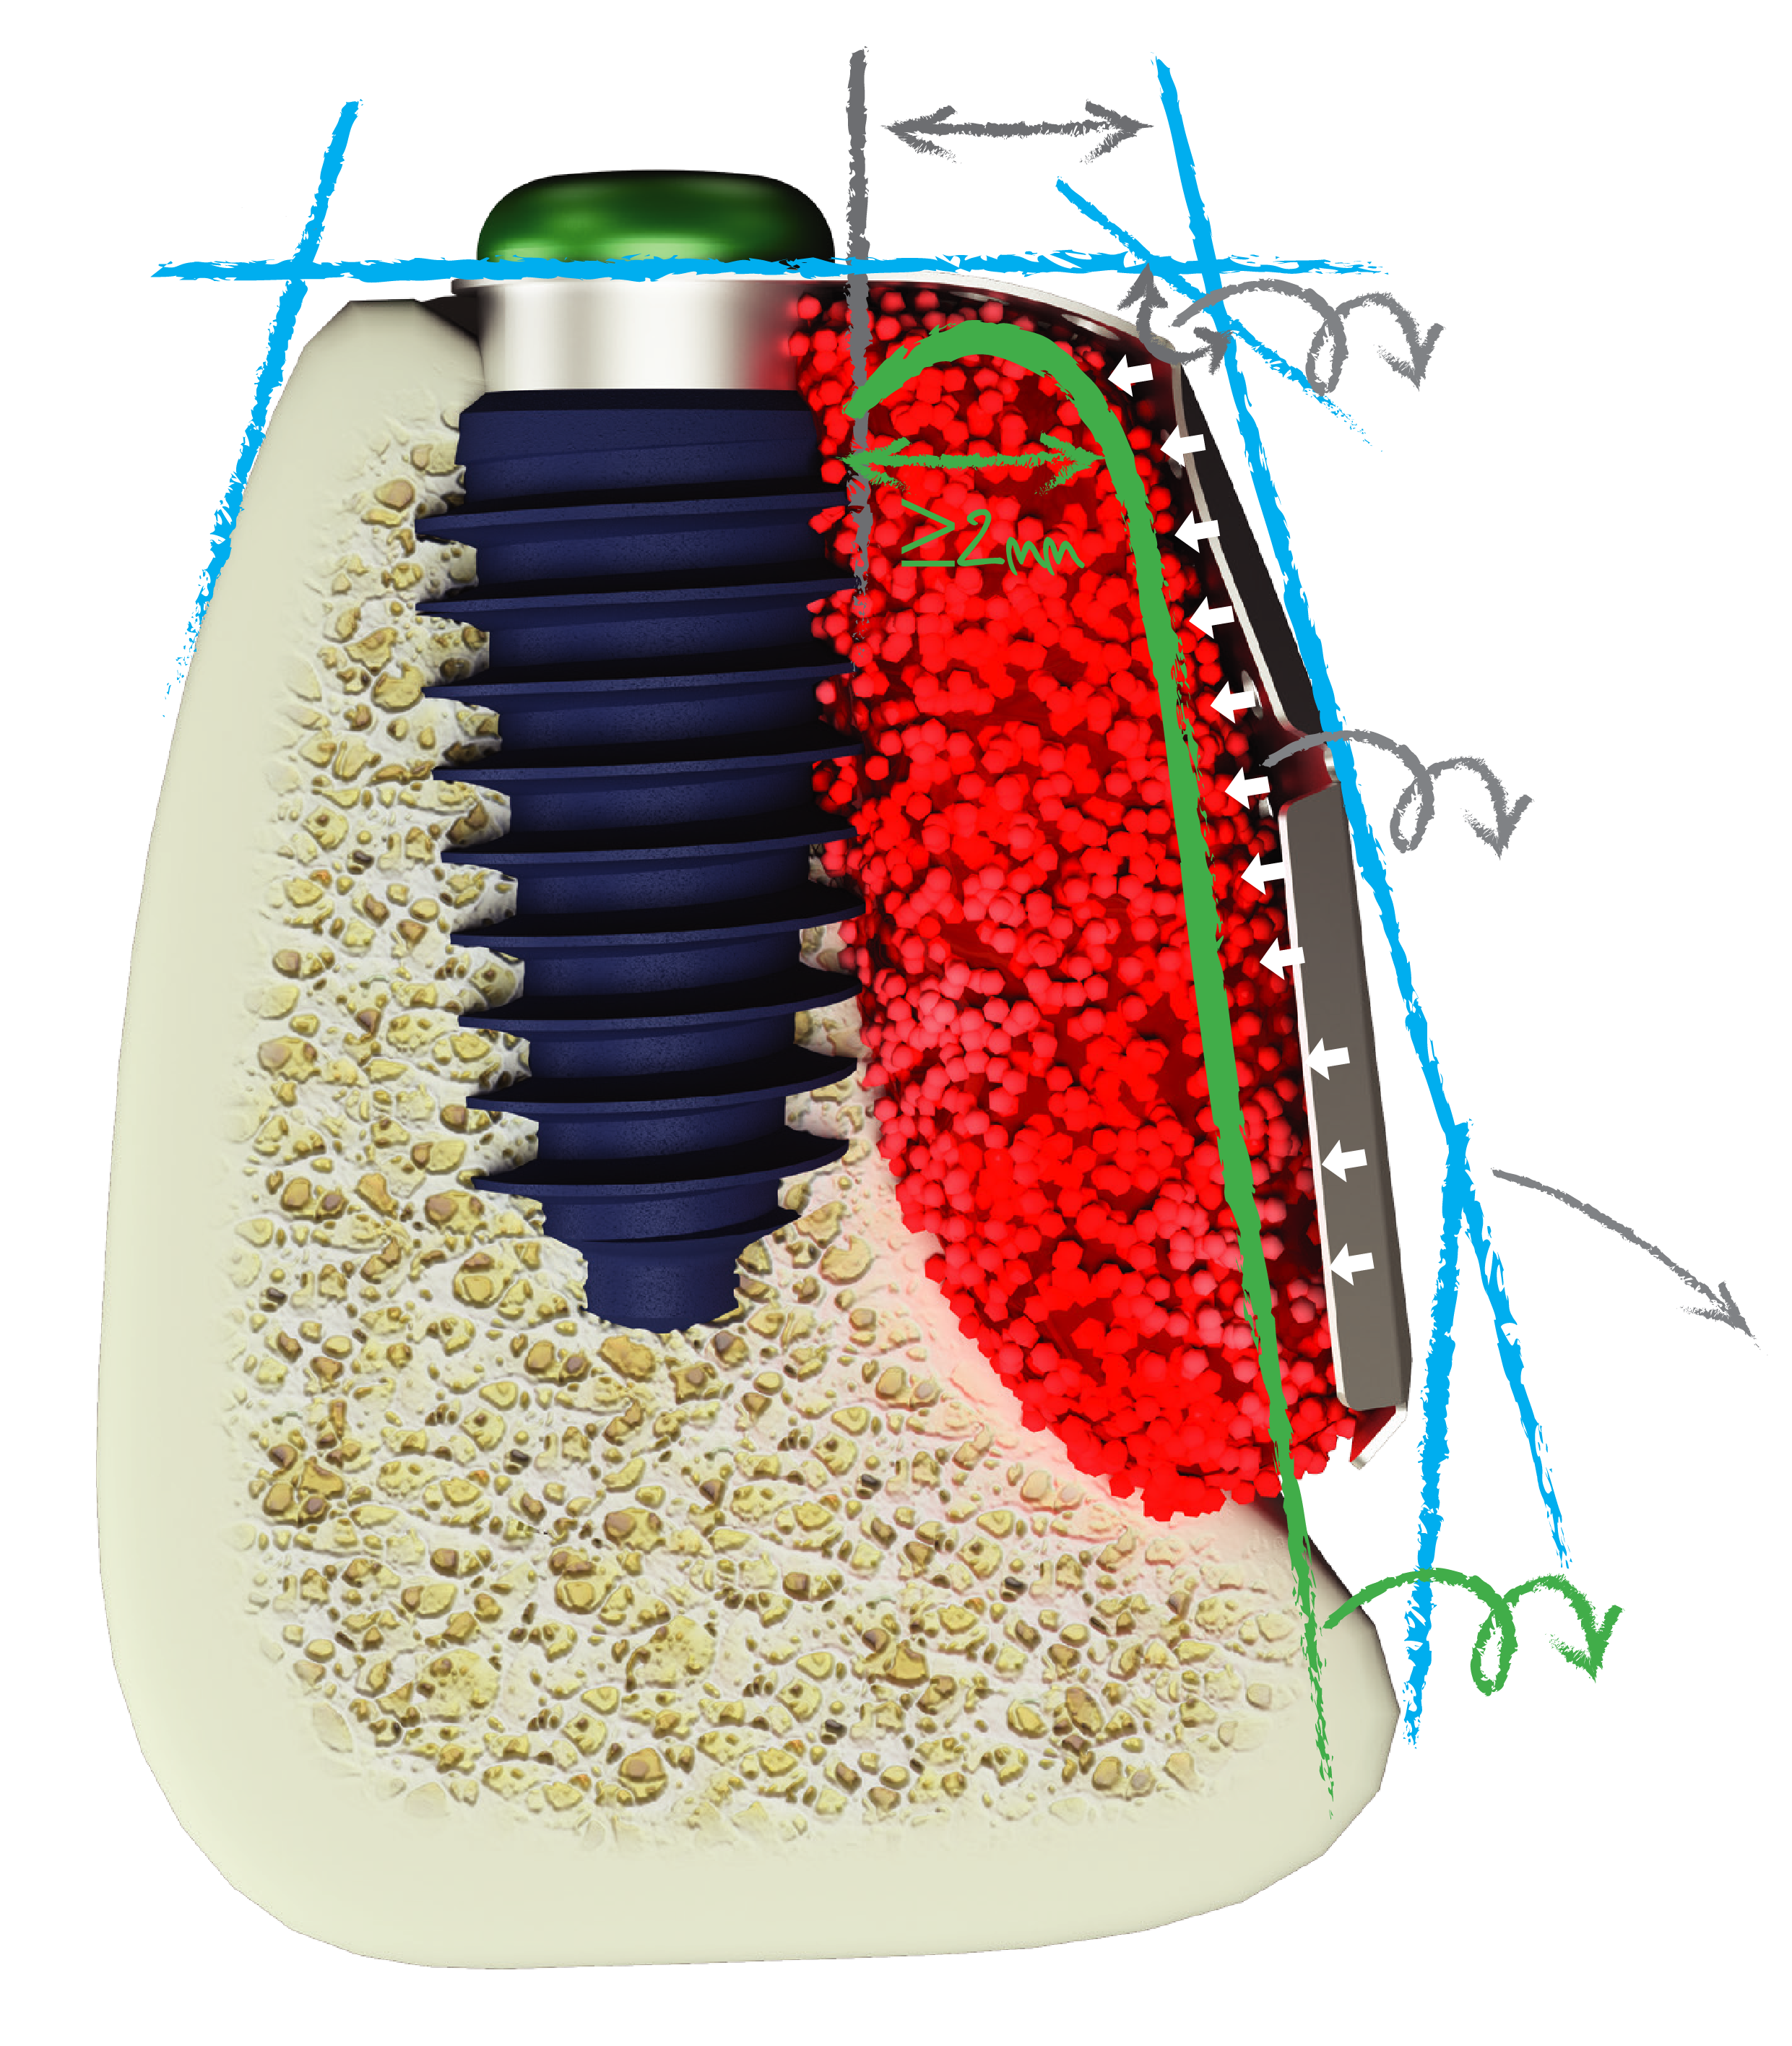

horizontal extension needed to make >2mm labial bone after remodeling.

with bevel should be made to avoid soft tissue irritation.

shrinkage will occur after removal membrane.

should be adapted to the bone

Any location, Any Size & Any Situation for GBR, i-Gen ensures regenerating minimum 2.5mm buccal bone. The regenerating of more than 2.5mm of buccal bone to minimize bone loss after GBR and maximize the life of implant.

Superior initial stability makes a perfect match for GBR using i-Gen membrane

AnyRidge can be placed in any ridge thanks to its knife thread. AnyRidge Knife thread has perfect stability in Regenerated bone.